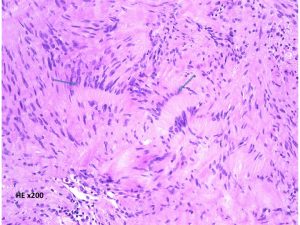

細胞核の柵状配列 (矢印 nuclear palisading). HE x200

紡錐型の核を有する腫瘍細胞で構成されます。左側の写真のように,古典的病理所見として,束状 fascicular に配列する密な組織である Antoni A Typeと網状 reticular で疎な組織である Antoni B Typeが混在するパターンを示します。神経鞘腫では多少の核の異型性がみられても悪性像とはいえません。嚢胞を形成したり,時には毛細血管拡張 simple hemangioma を思わせるような著明な血管の増生があり腫瘍内出血をきたすことがあります。

隣り合う細胞核の柵状配列 nuclear palisade arrangement (palisading) は,髄膜腫との鑑別での大切な所見です。